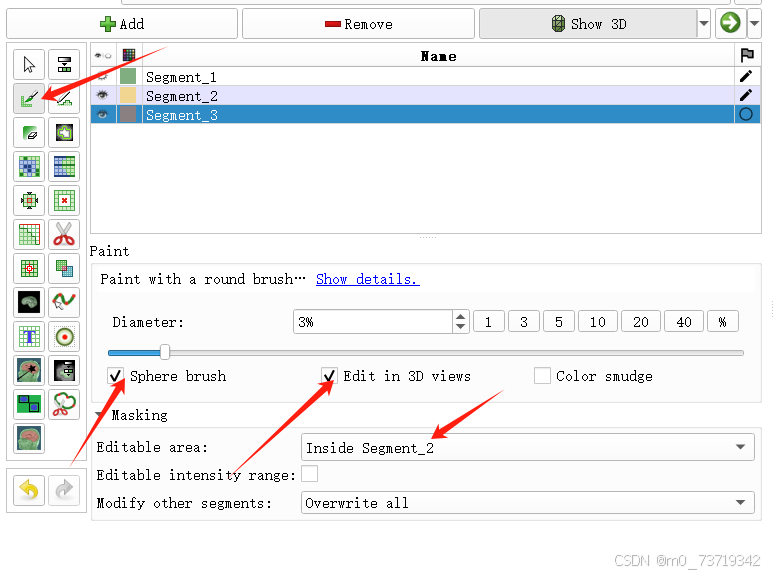

5.三维球刷标出冠脉位置

新建标注3

依次点击如下按钮

在三维视图中拖拉球刷对冠脉进行标注(shift+鼠标滚轮调整球刷大小)